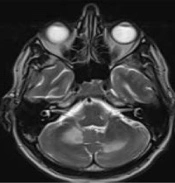

Steroid-Induced Progressive Multifocal Leukoencephalopathy (PML) in HIV Patient: A Paradoxical Effect